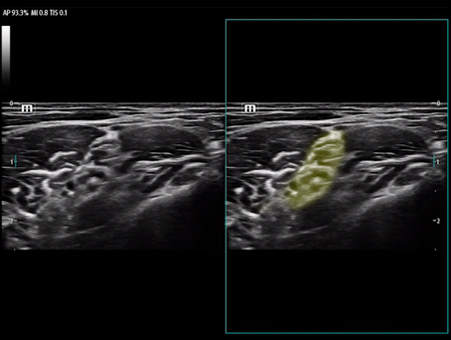

Reimagined safety and adaptability

MindrayŌĆÖs Anesthesia Ultrasound solutions address your biggest perioperative challenges such as treatment efficacy and patient safety, to improve patient outcomes in the operating room. We recognize the human side of healthcare and your role in providing best-in-class patient care, which is why we designed products suited to your clinical needs in this environment.